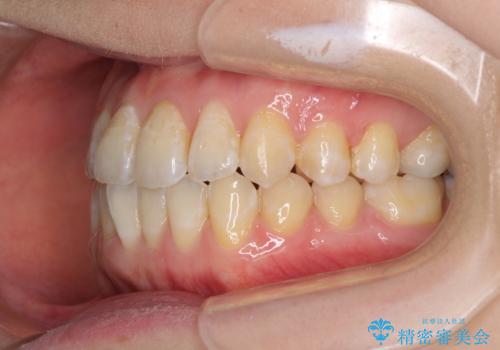

前歯のデコボコを治したい インビザラインによる矯正治療

- 前歯のデコボコを治したいとのことで来院された患者様です。

上下顎ともに歯列全体の後方移動とIPR(歯と歯の間を削る)によってデコボコが解消するように設計し、インビザラインにより治療を行うこととしました。